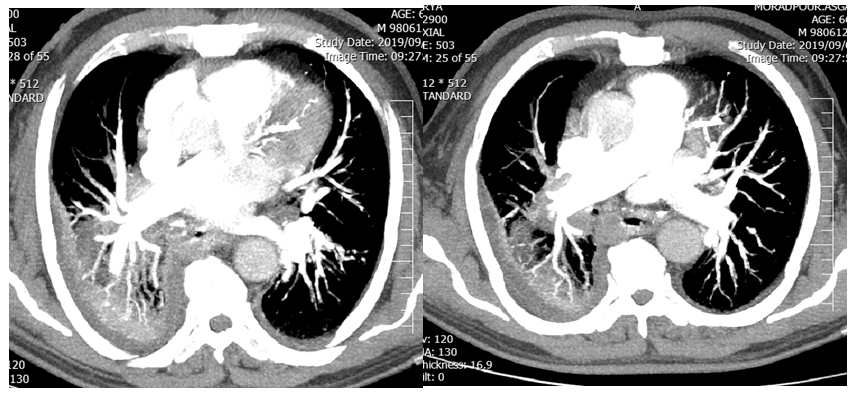

After patient’s stabilization, A chest CT-scan with IV contrast was performed. CT-scan showed a cavity in the right lung lower lobe which was connected to esophagus with leakage of contrast in the lumen (Figures 1 & 2). Urgent upper endoscopy was performed 12 hours after admission that revealed a huge clotted blood in the left-sided distal portion of esophagus. Blood clot was visualized and it was washed off and removed after irrigation, while an actively oozing blood vessel was the source of bleeding. Two days later, three episodes of hematemesis happened again so that the patient underwent re-endoscopy in which there was an orifice in the right side of esophagus from a cavity. At this time the diagnosis was fistula of esophagus diverticula to aorta, pulmonary parenchyma or heart chambers.

Figure 1 CT-scan with IV contrast shows a cavity in the right lung lower lobe which seemed to be connected to esophagus considering leakage of contrast in the lumen.

Figure 2 CT Angiography of pulmonary artery shows branch of pulmonary artery in the cavity, contrast around and in the lumen of esophagus.

We treated fistula by implanting a covered self-expandable metallic stent above the lower esophageal sphincter. Overnight, the patient had three additional episodes of hematemesis. At this point we were suspicious of pulmonary or aorta fistula to diverticula so that we performed a CT-angiograph of aorta and pulmonary artery. Aorta was intact, but fistula between diverticula and pulmonary artery was present (Figure 2). The patient underwent right postero-lateral thoracotomy; right lower lobe was severely adhesive to the mediastinum and esophagus. After pneumolysis, right lower lobectomy was performed and huge diverticula was present as a cavity, because of sever adhesion of diverticula to mediastinum partial diverticulectomy was performed and remnant diverticula was closed.